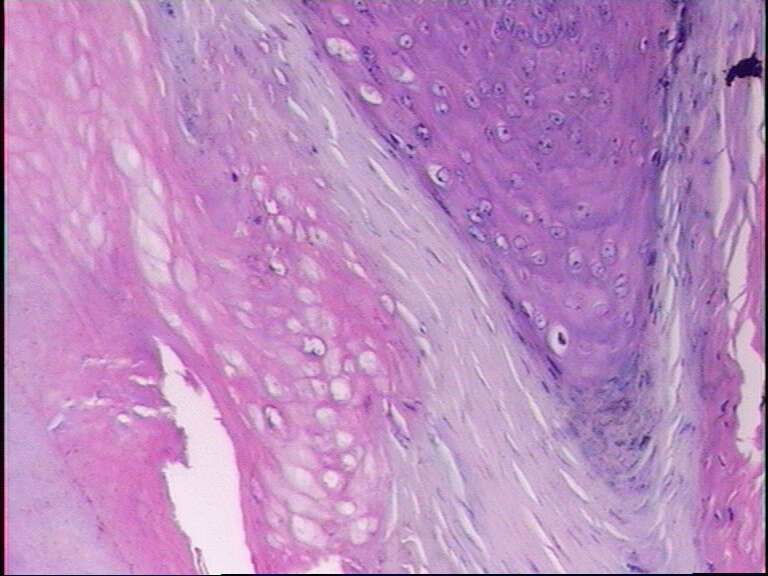

男38岁,手指肿物一年

寻常疣

典型的寻常疣病理改变。

寻常疣,图像比较典型的

乳头瘤样增生,空泡化细胞,典型寻常疣!最后一张典型的寻常疣构型!

寻常疣 肉眼间 皮肤局限性乳头状突起新生物。

镜下 表皮棘层增生,颗粒层增厚,角化亢进及角化不全,真皮乳头瘤病。颗粒层细胞空泡变性,其核内或胞质内有均质性嗜酸性蛋白小体形成,周围有空晕。角化不全的细胞科堆积成小山包样外观。

最后一张典型的寻常疣构型